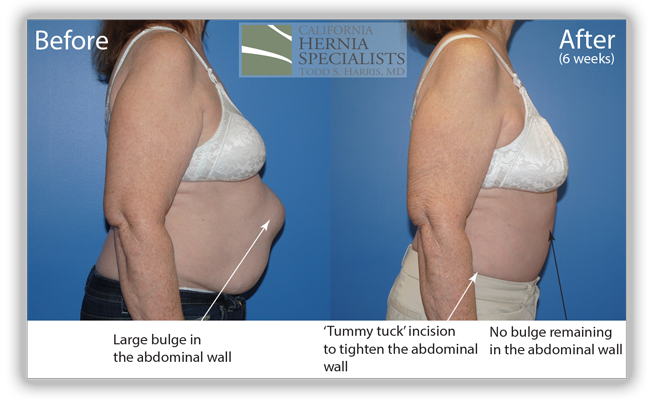

A 73 year old female had gallbladder surgery over 20 years ago. After that surgery she developed a small hernia at one of her incisions. This incisional hernia was repaired and she did well for over 10 years. Then the hernia returned and she underwent a second hernia repair. This only lasted for several years and the hernia returned. She had a 3rd attempt at hernia repair which only lasted several months before she noticed the bulge return.

She presented to California Hernia Specialists for evaluation and possible treatment. On examination it was clear that she had severe weakness of the muscles surrounding the hernia which was likely contributing to the repeated recurrences after her surgeries. Simply patching the hole in her muscle would not bring the healthy muscle back together and give her the best chance at preventing the hernia from returning. Thus laparoscopic hernia repair was not our recommendation.

Instead we discussed open hernia repair with a large incision to repair the damaged muscle and to remove excess skin and fat once the muscle was repaired. Below are a number of pictures including before and after photos, as well as photos taken during her surgery.